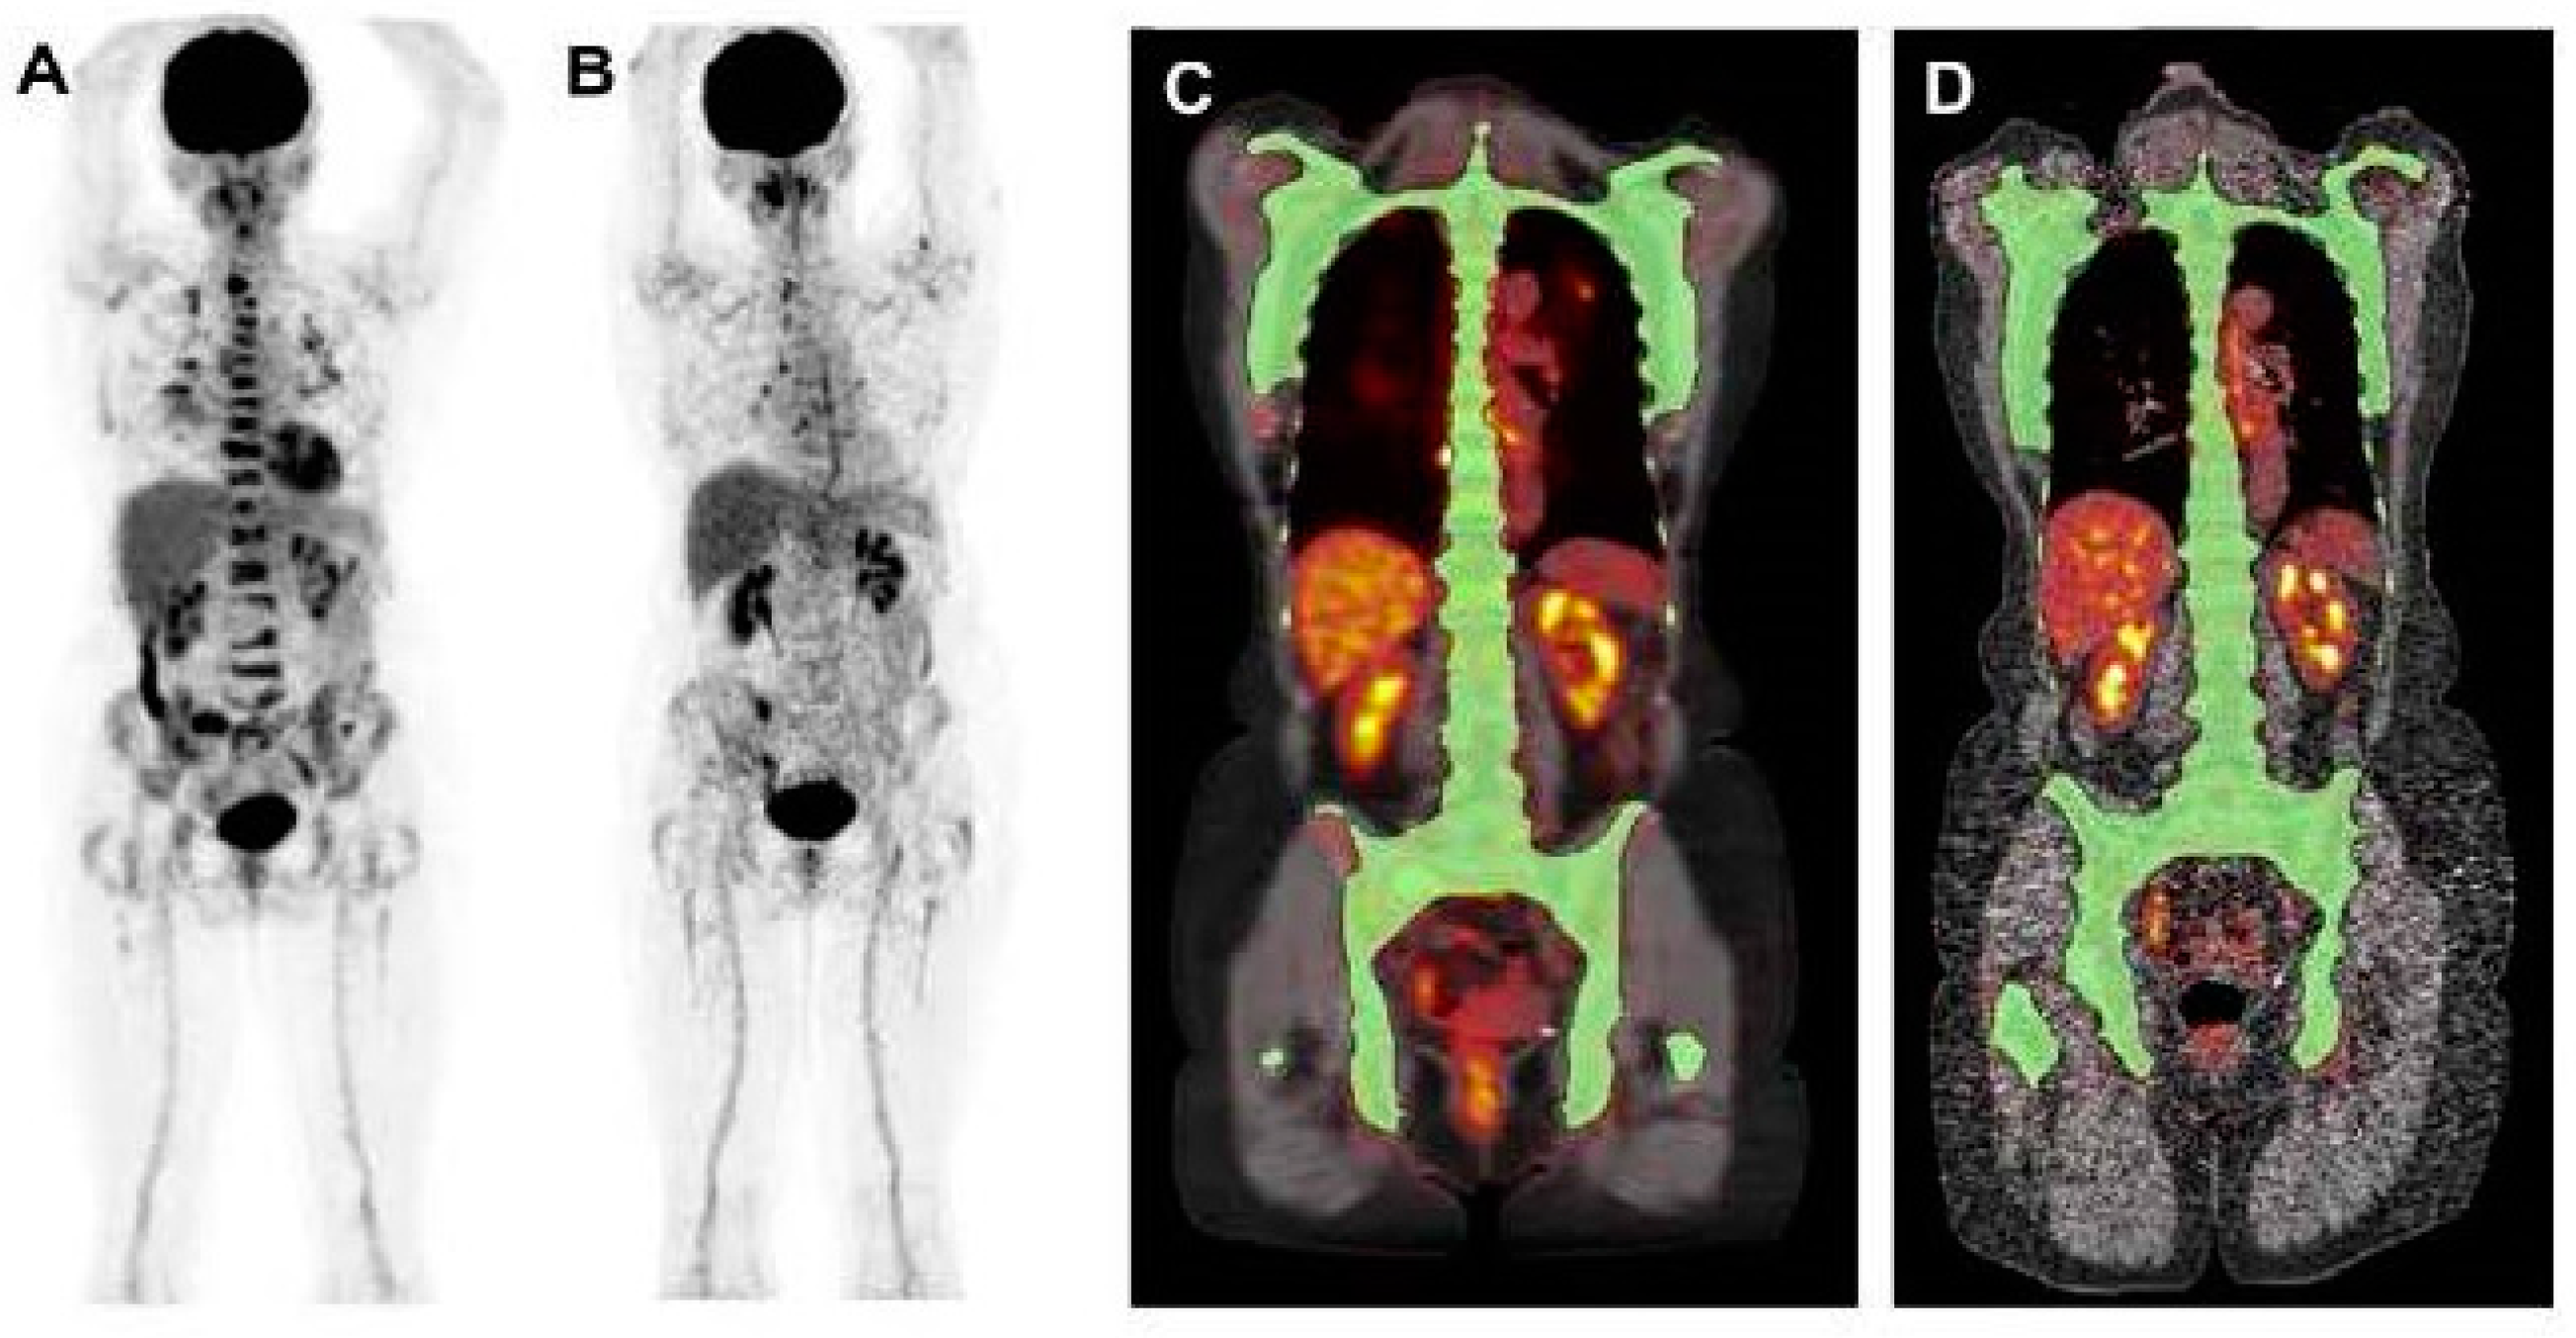

10. [18F]FDG PET Quantification

13. AI for PET Quantification

- Sachpekidis, C.; Enqvist, O.; Ulén, J.; Kopp-Schneider, A.; Pan, L.; Jauch, A.; Hajiyianni, M.; John, L.; Weinhold, N.; Sauer, S.; et al. Application of an artificial intelligence-based tool in [18F]FDG PET/CT for the assessment of bone marrow involvement in multiple myeloma. Eur. J. Nucl. Med. Mol. Imaging 2023, 50, 3697–3708. [Google Scholar] [CrossRef] [PubMed]